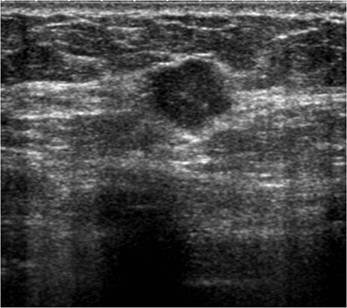

Localitzar la lesió mitjançant el transductor de l’ecògraf.

La peça es remet al servei de radiologia, es realitza una ecografia de la peça quirúrgica. L’objectiu és comprovar que la lesió estigui inclosa i que no s’hagin d’ampliar els marges quirúrgics.